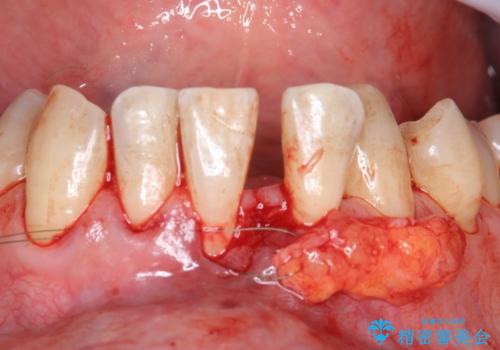

- 矯正前に下顎前歯の歯肉退縮の改善と予防のために歯肉移植を行った症例です。

上顎口蓋部から結合組織を採取し、下顎前歯部に移植しました。